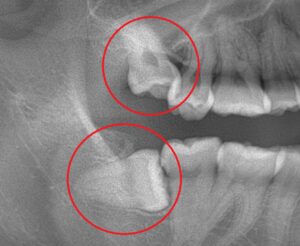

古代は食物の調理法が少なかったことから食物を硬いまま食べることが多かったため、顎の強い力が必要でした。しかし次第に軟らかい物を食べる機会が増え、食生活は変化していきました。これにより硬い物を噛み砕く、古代のような顎の力は不要になり、それに伴い顎の骨も小さくなっていきました。しかし歯の大きさはほとんど変わっていないため、歯の大きさに対する顎のスペースが足りず、親知らずが斜めになって生えてくることが多いようです。

このようにスペースのない顎の中で斜めに生えていたり、骨の中で水平に埋まっていたりすると前の歯を押してしまい、歯並びが崩れてしまうこともあります。